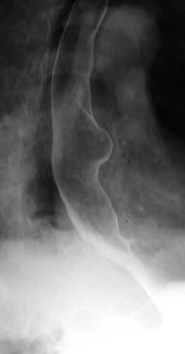

Achalazia cardiei